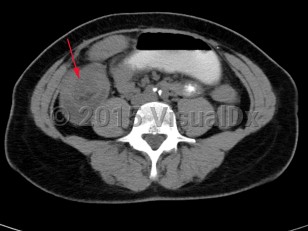

Intussusception is a telescoping or invagination of a part of the intestine into the lumen of an adjacent segment. Intussusception can present with variable severity. It can present with bowel ischemia and perforation with need for emergent surgical intervention, or it can present as relaxing / remitting abdominal pain of unclear etiology with intermittent symptoms and no signs of systemic illness. Jejunojejunal, jejunoileal, ileoileal, ileocolonic, and colocolonic are all types of intussusception that can occur, with the majority involving the small intestine.

Initial management requires ensuring hemodynamic stability, as many patients are dehydrated, and assessing concern for bowel perforation, which could require broad-spectrum antibiotics and urgent surgical intervention. Air or barium enemas can be both diagnostic and therapeutic. However, intussusception will frequently recur, in which case surgical resection is often required. Further imaging (ie, small bowel x-ray series, CT or MRI abdomen) can be utilized to identify the etiology if it is unknown based on presenting symptoms and a barium / air enema.